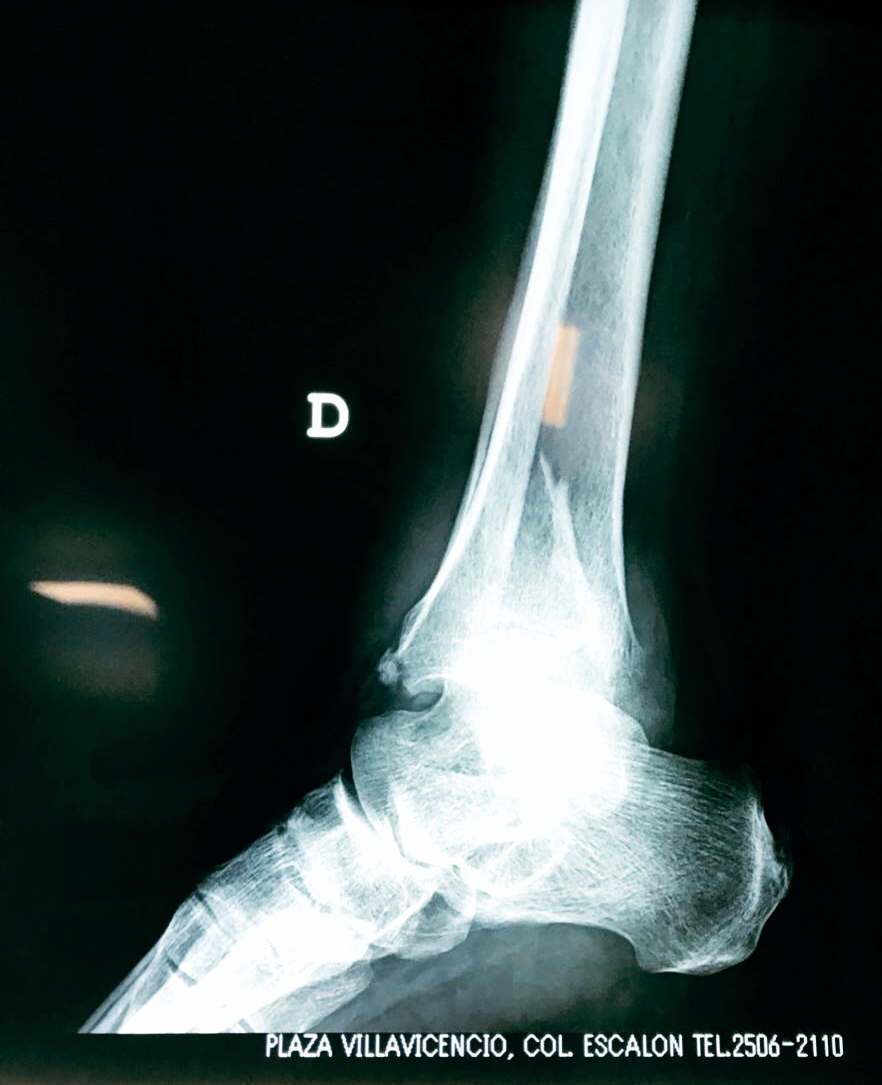

Una fractura de tobillo es la rotura de uno o más de los huesos del tobillo. Estas fracturas pueden ser:

- Parciales (el hueso está sólo parcialmente fisurado, no del todo).

- Completas (el hueso está perforado y está en 2 partes).

- Producirse en uno o ambos lados del tobillo.

Algunas fracturas de tobillo pueden requerir cirugía si:

- Los extremos de los huesos están desalineados entre sí (desplazados).

- La fractura se extiende hasta la articulación del tobillo (fractura intra-articular).

Cuando se necesita cirugía, es probable que esta implique el uso de clavijas de metal, tornillos o placas para sostener los huesos en su lugar mientras la fractura se consolida. Los elementos de soporte pueden ser temporales o permanentes.